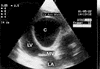

A 25-year-old woman, pregnant for 38 weeks, was admitted to our clinic with dyspnea. Transthoracic echocardiography revealed a large cyst that originated from the left side of the interventricular septum, decreasing left ventricular volume and almost entirely obstructing the left ventricular outflow tract. Cardiac magnetic resonance imaging confirmed a grade 1 hydatid cyst, which measured 61 x 59 x 66 mm. The cyst was excised after cesarean section. Extirpation required the creation of a small septal defect, which we closed without a patch, by suturing the septum directly to the left ventricular wall. The patient was discharged without symptoms. The case reported here is of particular interest not only because a hydatid cyst is rarely seen in the interventricular septum, but because a giant hydatid cyst obstructing the left ventricular outflow tract is very rare in pregnancy.